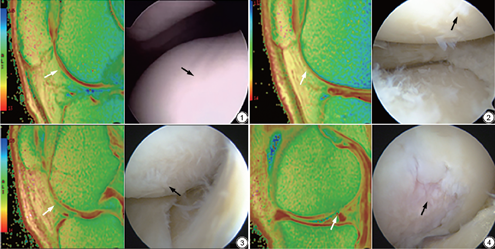

KOA组:选取2018年9月到2020年2月因膝关节不适等症状来我院就诊,经关节外科医生诊断为KOA并入院治疗(关节镜手术)的受检者(排除体质量指数大于28 kg/m2,有膝关节手术史、存在膝关节感染和肿瘤病史等) 54例,女性30例,男性24例,共72个膝关节。关节镜下软骨损伤的标准采用Outerbridge[7]分级(图1, 2, 3, 4)。

应用GE-ADW 4.6工作站,Functool 2 T2 MAP功能选项将矢状位T2 mapping原始图像生成T2伪彩图。由2名影像科骨肌组副主任医师运用Functool 2 T2 MAP功能选项自带的勾画组件,在T2伪彩图中的股骨关节面下、胫骨平台及髌骨表面3处关节软骨画取损伤范围ROI并标记国际软骨修复学会(International Cartilage Repair Societ,ICRS)[8] MRI分级(图1, 2, 3, 4),因Ⅳ级骨性关节炎中软骨全层缺失,软骨下骨裸露,无法测得软骨的纹理特征参数,本次研究对Ⅳ级损伤不做分析。选取MRI ICRS损伤分级与关节镜分级一致的201个关节面图像。